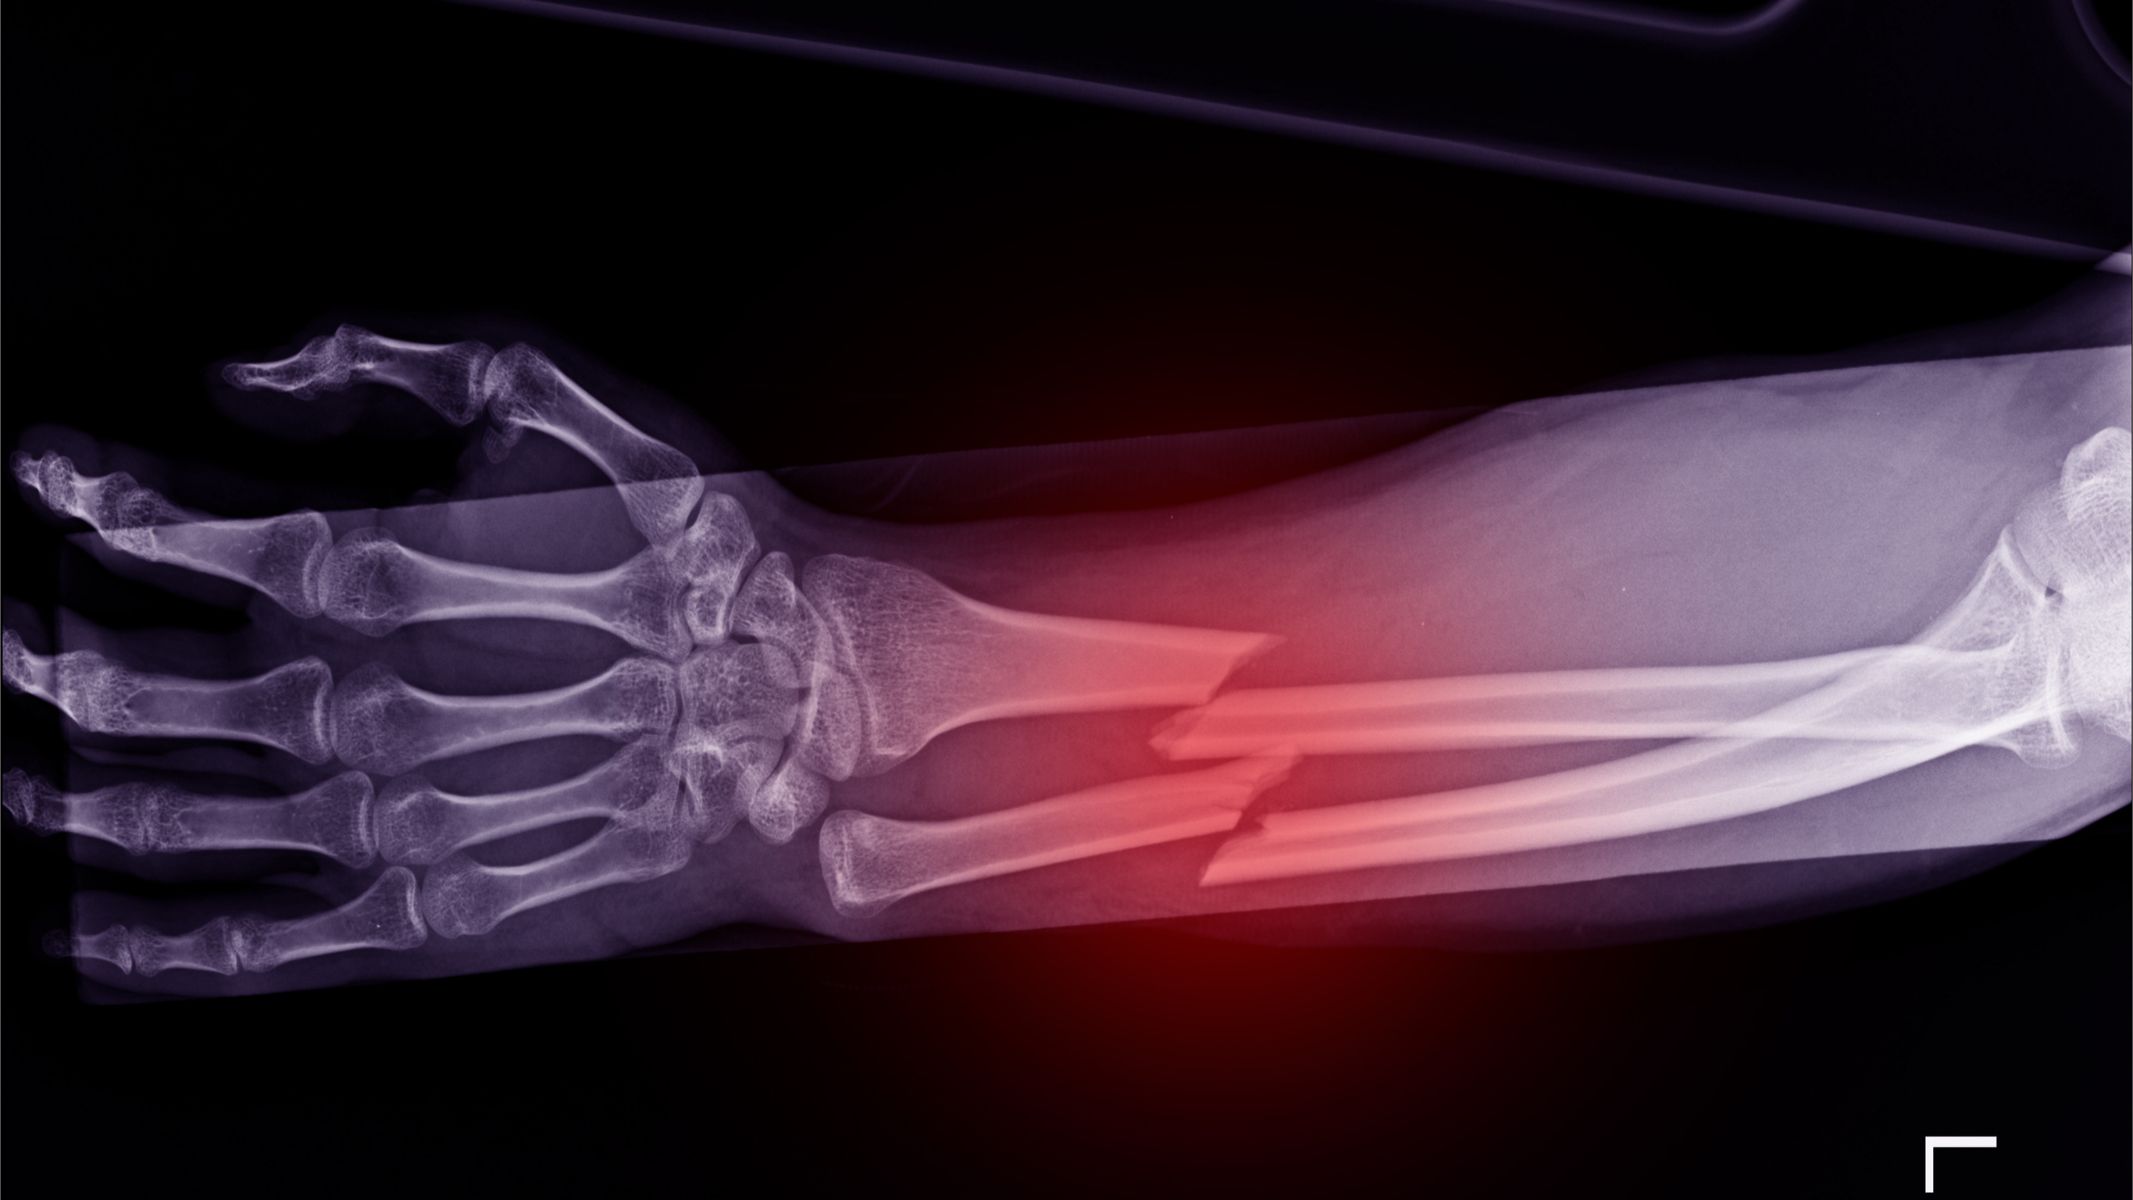

Gãy xương bệnh lý

Do cấu trúc xương bị phá hủy, người bệnh dễ bị gãy xương dù chỉ với tác động nhẹ. Gãy bệnh lý thường xảy ra ở xương đùi, cổ xương đùi, xương cánh tay hoặc cột sống. Khi xương gãy, người bệnh mất khả năng vận động và cần can thiệp y khoa ngay.

- X-quang xương: Phim X-quang có thể phát hiện vùng tiêu xương hoặc tạo xương bất thường. Đây là bước sàng lọc ban đầu nhưng đôi khi không phát hiện được tổn thương nhỏ.

- Phẫu thuật chỉnh hình: Khi xương yếu hoặc đã gãy, phẫu thuật cố định xương giúp người bệnh giảm đau và sớm phục hồi vận động. Các phương pháp gồm đặt đinh, nẹp vít hoặc thay khớp tùy vị trí tổn thương.